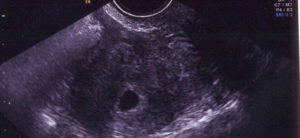

Однако ребенка на таком раннем этапе еще не видно – полноценного зародыша пока просто не существует. Поэтому ультразвук сможет показать будущего малыша в матке не раньше 3-5-й недель. На мониторе плодное яйцо смотрится как маленькая черная точка в маточной полости (обычно в верхней части). Сам эмбрион представляет собой небольшое образование белого цвета.

УЗИ 3 недели

На второй неделе после зачатия плодное яйцо имплантируется в маточную полость. При ТВУЗИ в матке на фоне «сочного» яркого слизистого слоя начинает визуализироваться округлое или овоидное анэхогенное, то есть черное, включение с ободком толщиной 0,1 см. Размер плодного яйца в этот срок равен 0.2 см в диаметре.

На третьей неделе после зачатия, то есть на пятой акушерской неделе, плодное яйцо достигает величины 0,6-1,0 см. Внутри него появляется желточный мешок, необходимый для питания эмбриона. На этом сроке плодное яйцо растет в диаметре примерно на 1 – 2 мм каждый день и визуализируется в проекции утолщенного эндометрия.